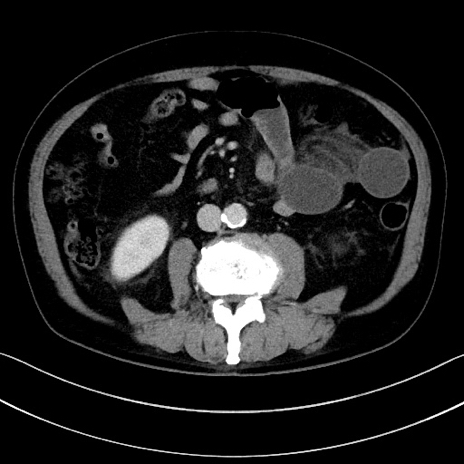

症例15(横断像)

【症例】70歳代男性

【主訴】腹痛

【現病歴】今朝から腹痛あり。全体的に痛い。特に左上の方。排ガスが今日はない。冷や汗が出る。

【既往歴】直腸癌術後

【身体所見】左側腹部〜上腹部に圧痛あり。腹膜刺激症状明らかなではない。軽度反跳痛。左下腹部に術後瘢痕あり。

【データ】WBC 7700、CRP 0.02